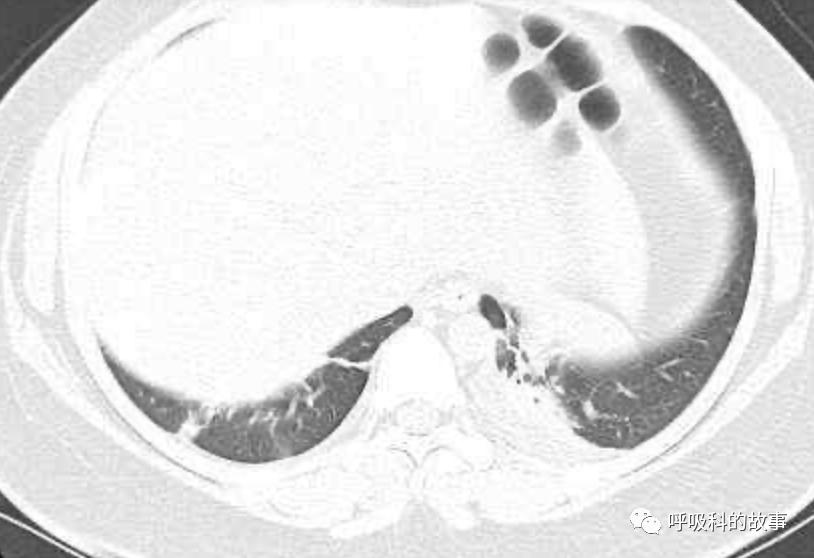

上面三张图分别是第一、二、三周的体温单

以下分别是血白细胞、CRP和转氨酶的变化曲线: